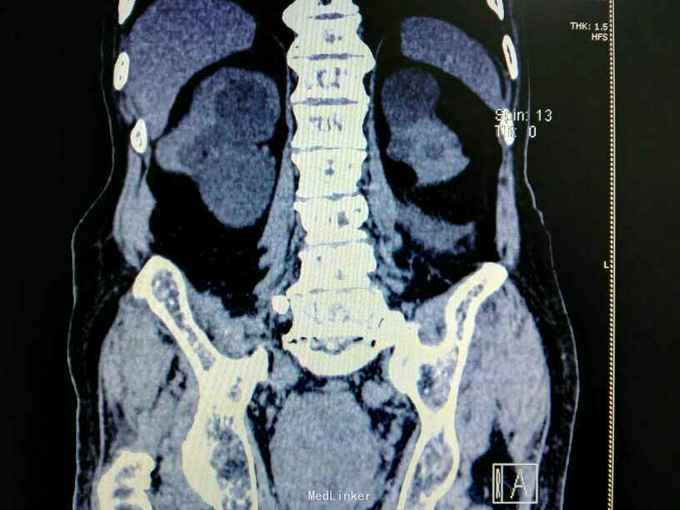

男性,87岁,进行性排尿困难10年,小便不能自解2天入院。无血尿,无发热、腰痛。一直口服藏药治疗前列腺增生症。既往无高血压、糖尿病。

腹部明显膨隆。耻骨上膀胱区扣浊。肾区无扣痛。尿常规少许白细胞。肌酐506,电解质正常。Hb116。

前列腺增生症 尿潴留 双肾积水 肾功能不全,膀胱结石,尿路感染,双肾多发囊肿。给予留置导尿,间断分次放尿后,出现肉眼血尿,持续膀胱冲洗,颜色较红,伴血凝块间断堵管。